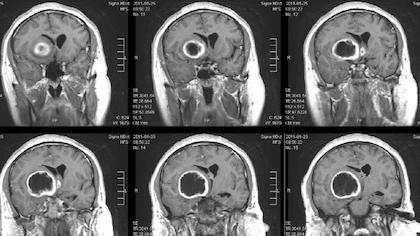

DALLAS – April 23, 2020 – A combination of immunotherapy agents that encourages some immune cells to eat cancer cells and alert others to attack tumors put mice with a deadly type of brain cancer called glioblastoma into long-term remission, a new study led by UT Southwestern scientists suggests. The finding , published online March 20, 2020, in Nature Communications , could lead to new therapies that may significantly extend survival for human glioblastoma patients, which stands at an average of 15 months after diagnosis even with current state-of-the-art therapies.

Some pharmaceuticals in development aim to boost the innate immune system’s action against cancer by blocking CD47, a protein that many cancer cells display on their surfaces that functions as a “don’t eat me” signal. Glioblastoma (GBM) – the most common primary central nervous system malignancy in adults and a cancer that Jiang frequently treats in clinic – often displays substantially elevated amounts of CD47 on its tumor cell surfaces, with higher amounts generally suggesting worse outcomes for patients. But these drugs have had mixed results in clinical trials, Jiang says; although they’ve shown promise for blood cancers, such as leukemias, their performance for solid tumors has been disappointing.

When the researchers tested this combination therapy in a mouse model of GBM, it successfully shrank tumors and extended life. However, in time, the tumor cells developed a different way to evade the immune system by boosting their production of a protein called PD-L1, which shields them from T cell attack. Thwarting this move, the researchers added an antibody against this protein called anti-PD-1. Together, this three-part regimen – anti-CD47 antibodies, TMZ, and anti-PD-1 antibodies – dramatically extended survival. About 55 percent of these animals did not die over the course of the study, a scenario akin to long-term remission in patients, Jiang says. He and his colleagues hope to test this approach in humans soon in a clinical trial, he adds.